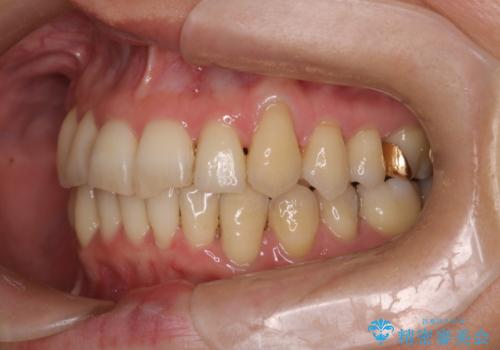

- 40代女性

- 2年4ヶ月

- 上下の歯の凸凹を主訴に来院されました。

他院では抜歯+ワイヤー矯正の提案をされているとのことでした。

当院での検査にて非抜歯+インビザライン矯正を提案させていただき治療を行なっております。